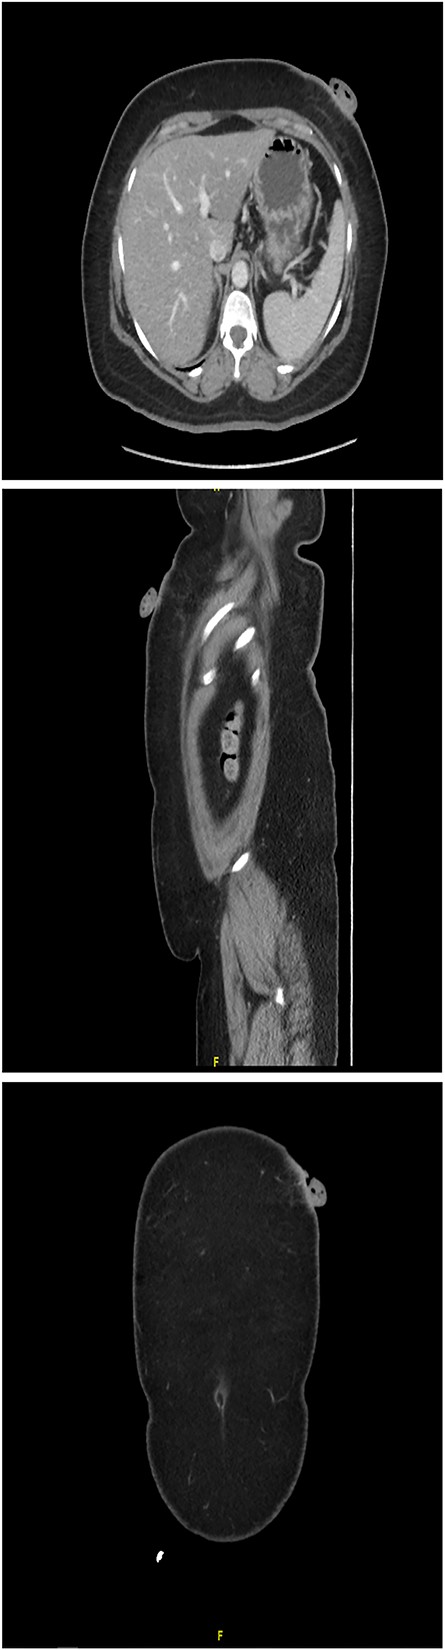

A 61-year-old woman with type 2 diabetes, hypertension and dyslipidemia presented to the authors’ hospital’s outpatient department with a left upper abdomen wall tumor that began as a tiny nodule and gradually enlarged over 15 years. The lesion caused pain, bloody leakage and skin changes around the mass. The patient denied having ever had a fever, weight loss, trauma or any family history of cancer. The patient was conscious, alert and not in pain during the physical examination. Local inspection revealed a brown mobile single mass in the left upper abdomen, shaped like a pedunculated polypoid measuring roughly 3 cm × 2 cm with an irregular border. An anterior left upper abdominal wall skin-based, pedunculated, enhancing soft tissue nodule with a giant stalk was seen on computed tomography (CT) scanned abdomen and pelvis (Fig. 1). The nodule measures 1.8 cm × 3.6 cm × 3.6 cm and has no free soft tissue invasion. Based on these observations, surgical excision and histological examination were carried out.

CT scanned abdomen and pelvis showing an anterior left upper abdominal wall skin-based, pedunculated, enhancing soft tissue nodule with a large stalk